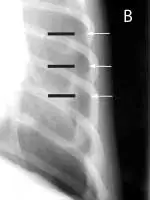

FIGURE 2

Signs of retraction of the lung lobes from the thoracic wall and blunting of the costophrenic angles (A) are best appreciated on the DV view (versus VD view) unless a large amount of air is present. Close-up of the DV view (B) shows air between the thoracic wall (white arrows) and lung (black arrows).